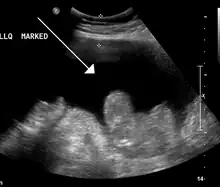

A Ecografia é usualmente utilizada na investigação do quadro previamente a medidas para remover o fluido da cavidade abdominal. Esta pode revelar as dimensões e forma dos órgãos intra-abdominais e estudos Doppler mostram a direcção do fluxo na veia Porta bem como detectar a Síndrome de Budd-Chiari ou a trombose da veia porta. Adicionalmente, o ecografista pode ectuar uma estimativa da quantidade de líquido ascítico e ascites de difícil drenagem podem-no ser sob controlo ecográfico. A Tomografia computadorizada Abdominal é um método mais sensível para revelar a estrutura e morfologia dos órgãos abdominais.